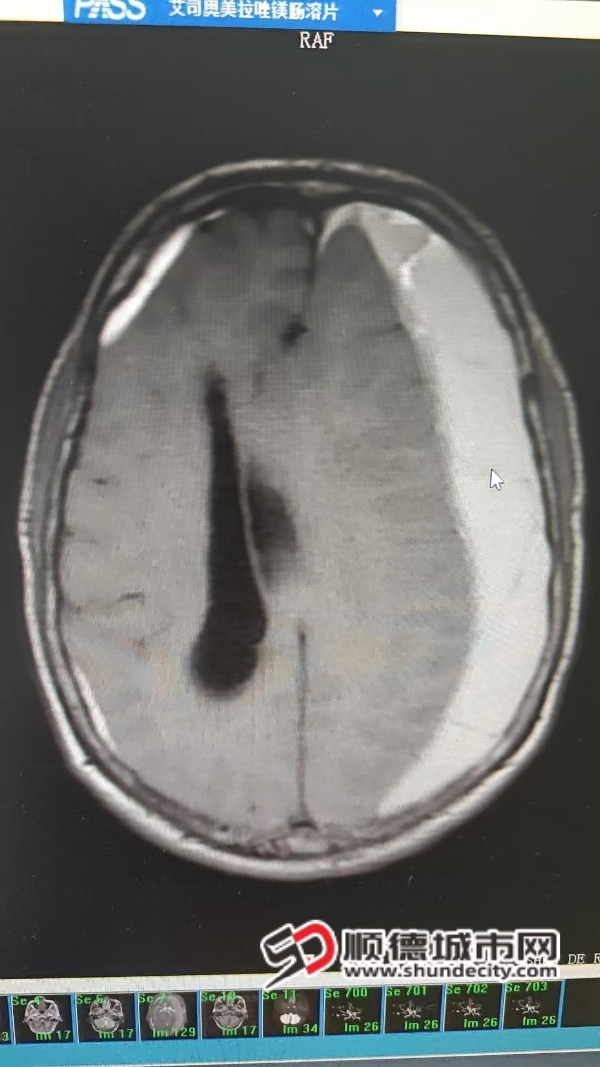

手术前。

头颅CT扫描是诊断慢性硬膜下血肿的金标准。能够快速、清晰地显示血肿的位置、大小、范围以及脑组织受压的程度。